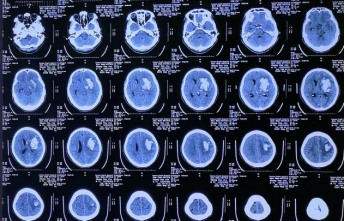

CT显示左侧基底节区不规则脑出血,有多处“岛征”

一开始计划“一洞双管”加速血肿排空。这是下方靶点。